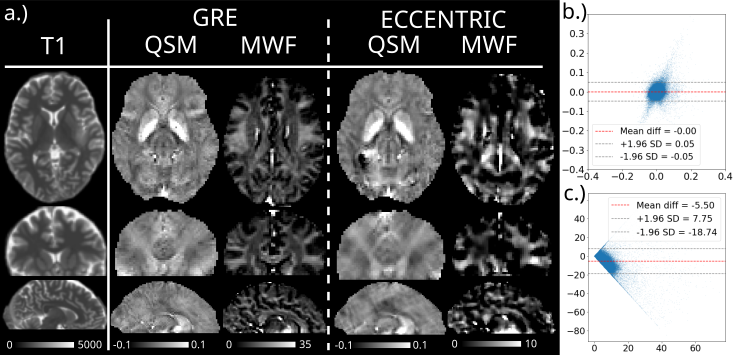

Figures 7 and 8 show a comparison of QSM and MWF in one healthy volunteer (Fig 7) and one glioma patient (Fig 8) obtained with ME-GRE and wu-MRSI ECCENTRIC acquisition. Similar spatial patterns of tissue susceptibility anisotropy can be noticed in the QSM maps obtained by both methods. Likewise water myelin fraction shows a distribution that is consistent with the white matter spatial distribution in both methods. The Bland-Altman comparison between the two methods for the quantitative values of tissue susceptibility and water myelin fraction reveals a very small bias and narrow limits of agreement.

Refer to caption

Figure 8: QSM and MWF imaging in a mutant IDH glioma patient obtained from ws-MRSI acquisition with ECCENTRIC at 2 mm isotropic resolution compared to gold standard ME-GRE. On the right Bland-Altman plots compare the values of QSM (b) and MWF (c) methods. T1 map [ms] is shown on the left.

WALINET+ provided the lowest NRMSE (<2%<2\%) in simulations and in vivo the smallest bias (<20%<20\%) and limits-of-agreement (±63%\pm 63\%) between wu-MRSI and ws-MRSI scans. Several metabolites such as creatine and glutamate showed higher SNR in wu-MRSI. QSM and MWF obtained from wu-MRSI and GRE showed good agreement with 0ppm/5.5%0\,\mathrm{ppm}/5.5\% bias and ±0.05ppm/±12.75%\pm 0.05\,\mathrm{ppm}/\pm 12.75\% limits-of-agreement.